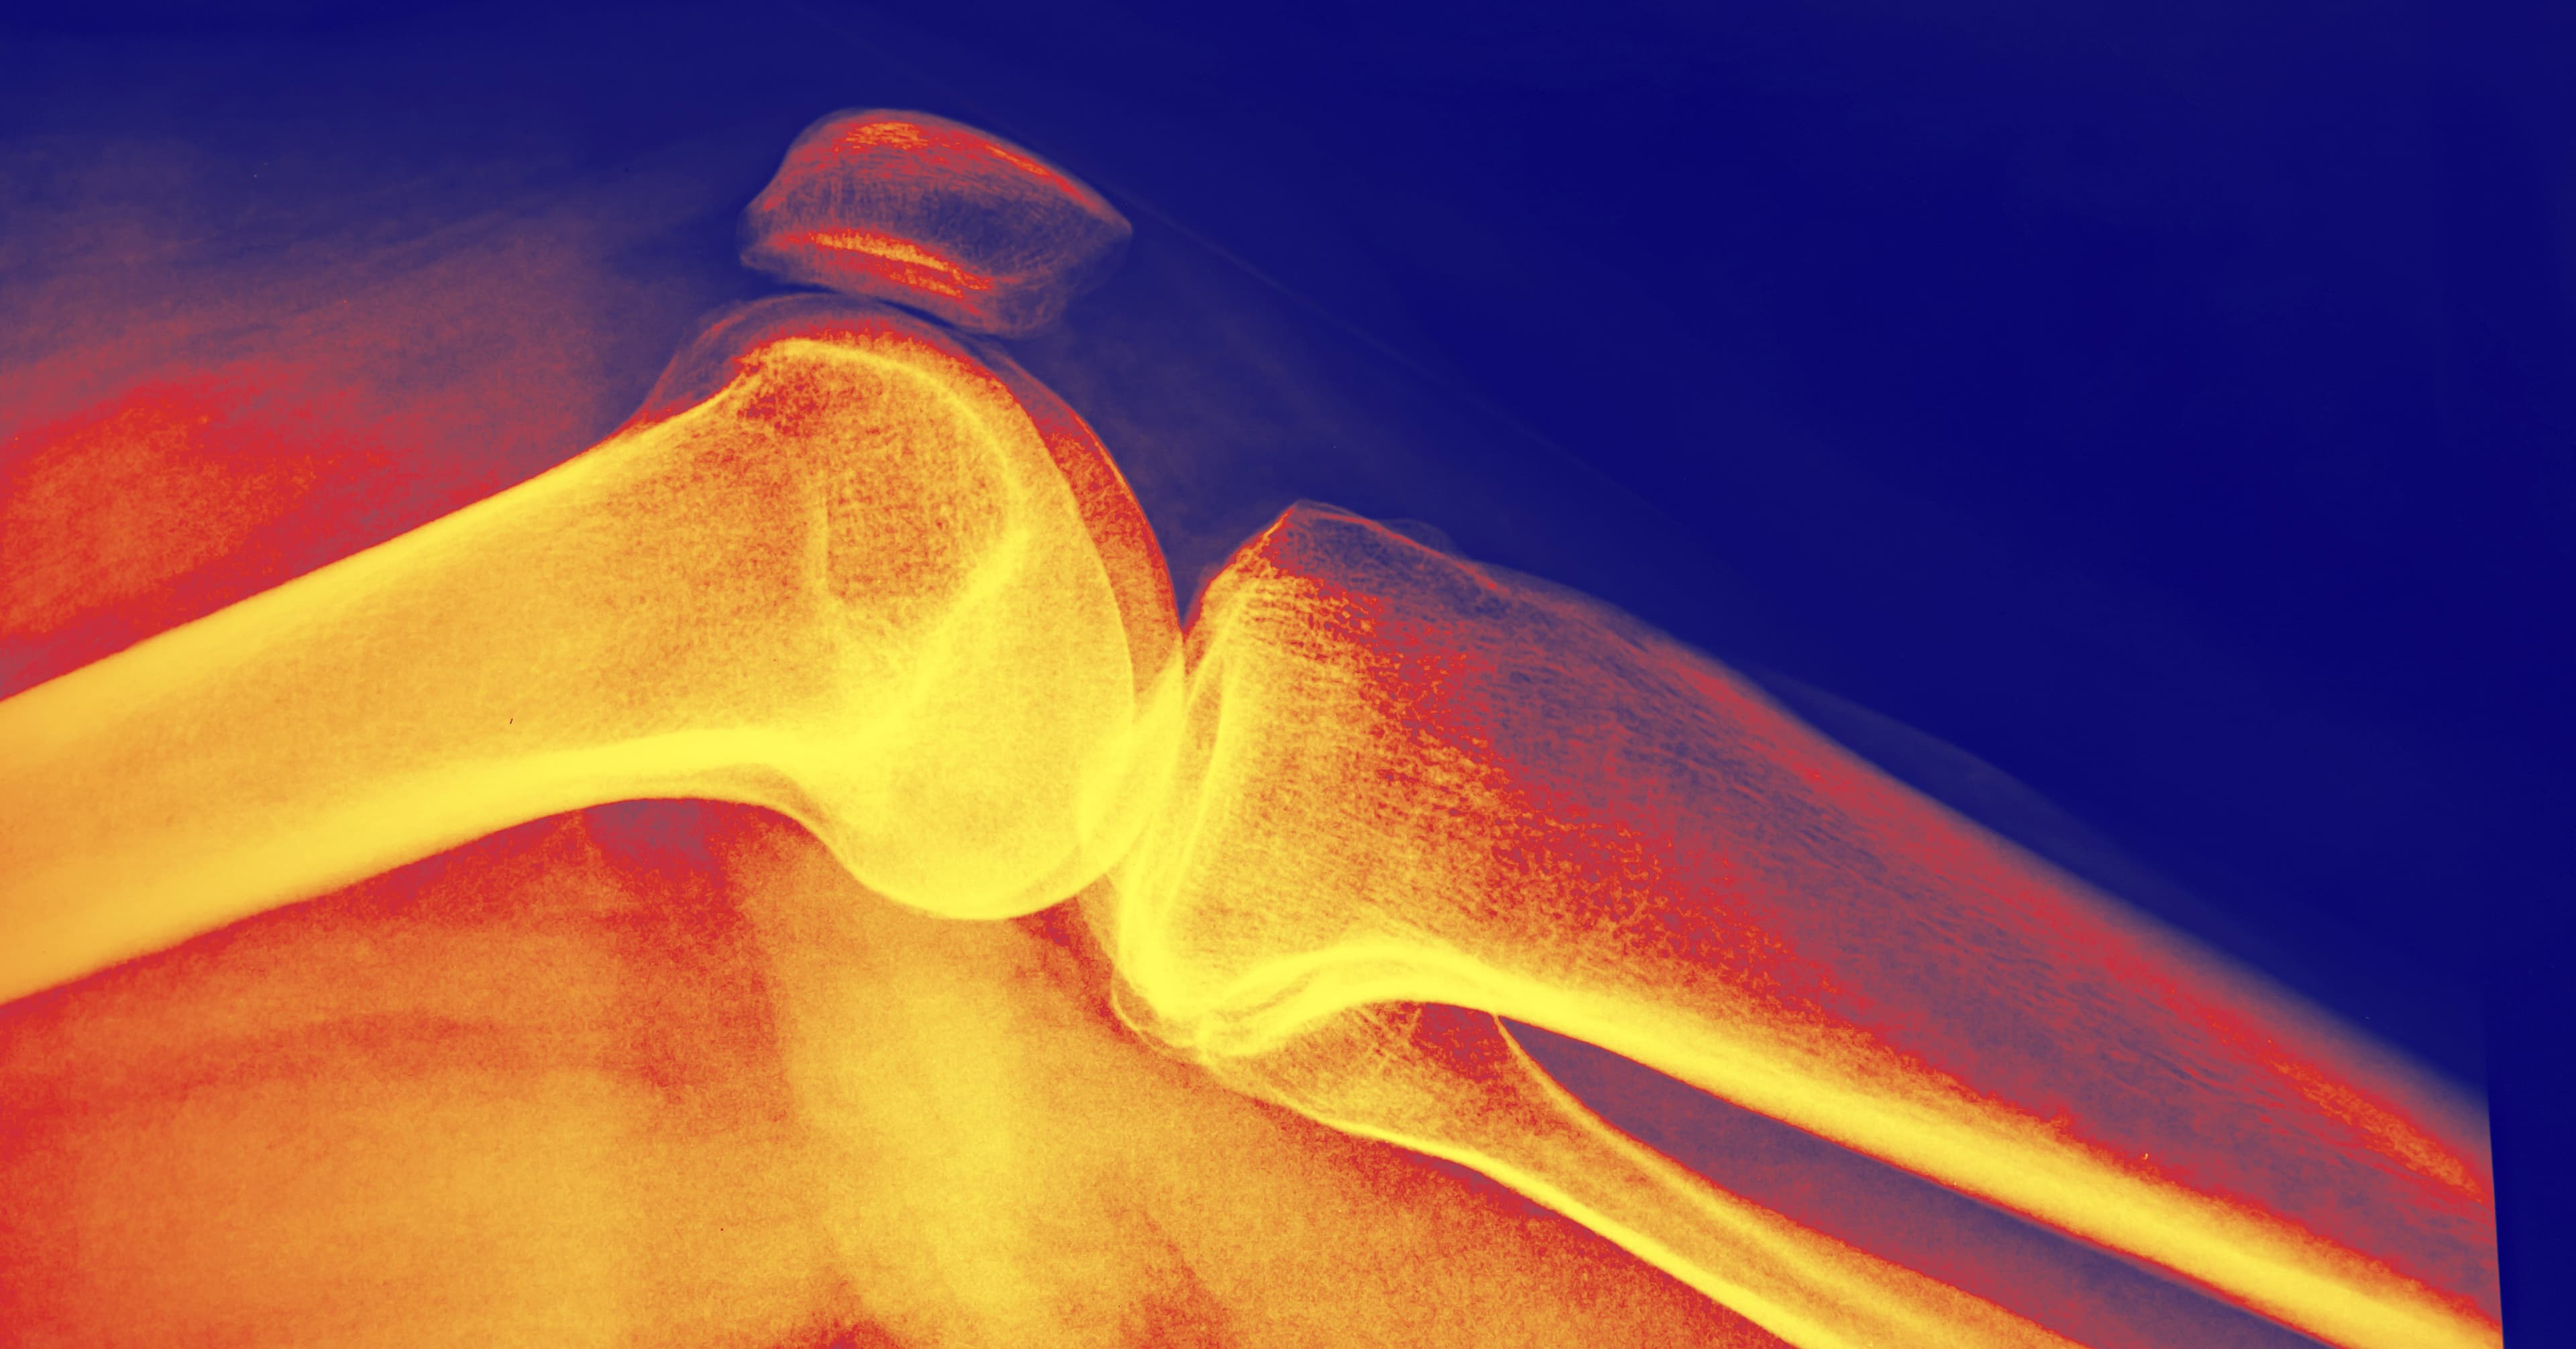

How Long Does It Take to Increase Bone Density?